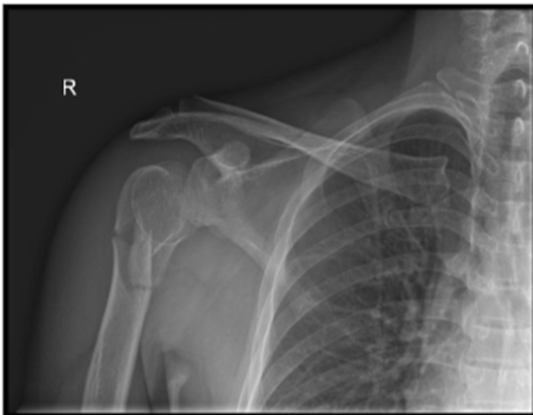

We present a 50-year-old Southeast Asian male who presented to the emergency department with right shoulder pain and deformity. This closed injury was sustained after colliding with a rock while cycling, in which the patient fell off his bike and landed onto his right shoulder. Neurovascular status was intact, and radiographs of the right shoulder revealed a 4-part right proximal humerus posterior fracture-dislocation with head split (AO Classification 11-C3) (Image 1). During the consultation, the options of surgical fixation and hemiarthroplasty (HA) were both explained to the patient. The risk of AVN leading to salvage arthroplasty was discussed for fixation, whereas the concerns of implant longevity and dislocation risk was discussed for arthroplasty. In view of the displaced fracture, shared decision making between surgeon and patient was made for surgery to facilitate early mobilisation. Considering the patient’s age and activity level, fixation will be attempted. However, the patient was counselled on the possibility of shoulder hemiarthroplasty should the intraoperative findings reveal a fragmented fracture pattern to prevent AVN, or an unfavourable fracture pattern in which fixation is unlikely to be successful. One key limitation of Hertel’s study to predict the risk of AVN is the presence of few young patients (mean age of the study participants were 60 years old) [18]. This also influenced the surgeon’s decision to offer joint preserving surgery to the patient. A computed tomography scan was not necessary since the severity of the fracture-dislocation is evident on radiographs.

A. Anteroposterior (AP) view

B. Valpeau view

C. Lateral/ Y scapula view

Image 1: Preoperative imaging of the right shoulder showing a right proximal humerus posterior fracture-dislocation with head split.